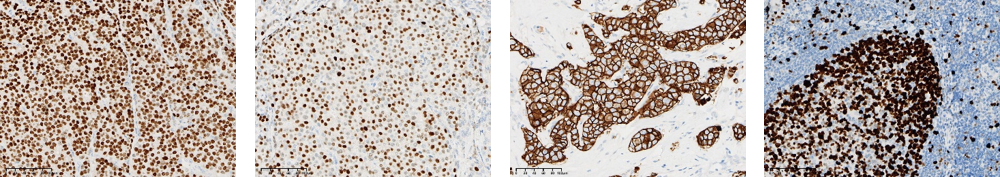

近日,熙寧生物|精翰生物參加中國(guó)非公立醫(yī)療機(jī)構(gòu)協(xié)會(huì)病理學(xué)專業(yè)委員會(huì)和國(guó)家病理質(zhì)控中心(PQCC)非公組聯(lián)合組織的特殊染色室間質(zhì)評(píng)活動(dòng),檢測(cè)指標(biāo)包括MSH2、MSH6、MLH1、PMS2、ER、PR、HER2、KI67、Claudin18.2、CD20、Bcl-2、Bcl-6、C-MYC、彈力纖維染色、粘液染色(AB[Ph2.5]法)、淀粉樣蛋白染色(剛果紅法),以上16項(xiàng)檢測(cè)指標(biāo)熙寧生物|精翰生物組織病理平臺(tái)均高分通過(guò),榮獲合格證書(shū)。

Claudin18.2

CD20

Bcl-2

Bcl-6

C-MYC